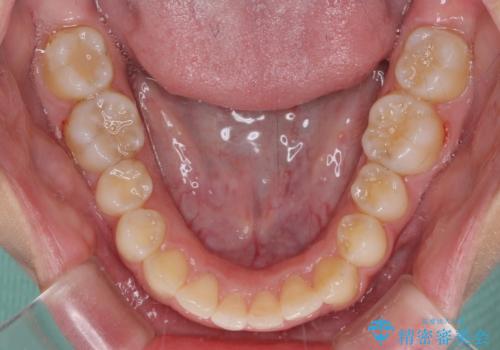

- 前歯の歯並びと不自然な色をした前歯のクラウンを気にして来院された患者様です。

上下前歯の歯列不正はインビザラインにより歯列を整え、その後に、前歯をオーダーメイドタイプのオールセラミッククラウンにて補綴治療することとしました。

前歯のデコボコを一番気にしていらっしゃいましたが、矯正治療により下顎前歯が隠れるほどのディープバイトも一緒に改善され、奥歯に負担のかかりにくい咬み合わせとなりました。